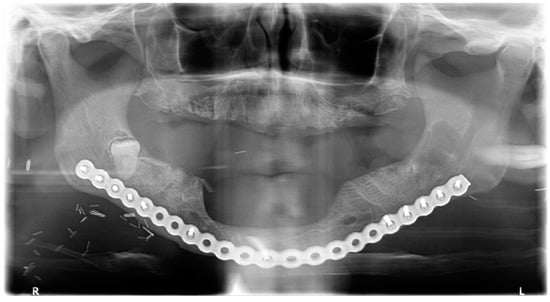

The lesion was enucleated in toto, and the teeth extracted (Figure 12) under general anesthesia, during which the ENT and maxillofacial surgeons proceeded with the placement of a mandibular osteosynthesis plate, followed by non-interruptive mandibulectomy, and finally, pelvi-glossectomy with tracheostomy and reconstruction with an anterolateral thigh flap and neck dissection. Histopathological examination of the cystic lesion allowed to diagnose a DC. The patient was followed regularly for two years, and no recurrence was observed.

Figure 12.

Avulsion of tooth 38 and in toto enucleation of the cyst in case #4.

Healing was uneventful and the patient had no complaints. Radiologically, at the 6- and 12-month follow-up (Figure 13), there was no reossification at the cystectomy and tooth 38 sites, which could be explained by a side effect of postoperative radiotherapy and chemotherapy. However, there were no signs of enlargement of the residual bone cavity, suggesting a recurrence of DC.

Figure 13.

CBCT X-ray of case 4 at one year follow-up.